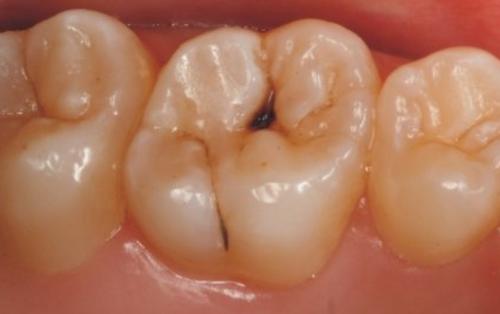

❶ 轻度龋齿

当牙齿有轻微的龋齿时,通常可以通过清洁和填充龋洞来恢复牙齿的健康。

❶ 严重龋齿

当牙齿龋坏严重,无法通过填充来修复时,可能需要拔除患牙。